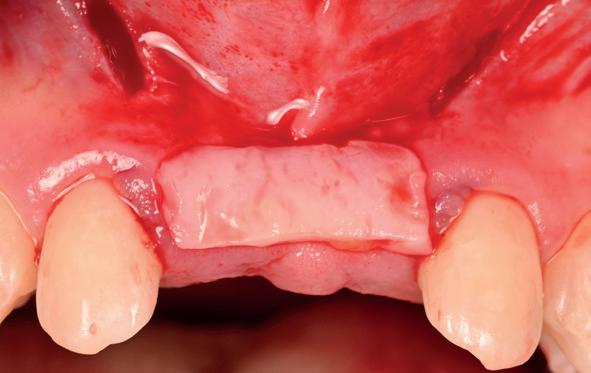

tinaal geslepen te worden als er geen 1,5 mm ruimte voor de vleugels behaald kan worden. De ruimte was op de dunste plekken 1 mm, dus een kleine preparatie in de 12 en 22 palatinaal was nodig. Omdat de kaak volledig afgevlakt was en dun was geworden, kunnen de dummies van de etsbrug enkel op de kaak “gelegd worden”, maar daarbij zijn er geen papillen en staat de cervicale rand van de dummies net voor de kaak. Een esthetisch resultaat kan daarmee niet behaald worden. Daarom is een aanvulling van de zachte weefsels in de breedte nodig, als het creëren van een emergence profile, waarbij het oogst alsof de gebitselementen uit het weefsel vertrekken.

Voor de aanvulling zachte weefsels chirurgie werd gekozen voor de VISTA techniek, hierbij worden er twee incisies partial thickness flap hoog in de mucosa gemaakt, waarna er ruimte vanuit de incisies wordt getunneld tussen de gingiva en het periost door middel van VISTA tunnel instrumenten. Uit het palatum links werd een vrij gingivatransplantaat geoogst van 15x10 mm met een dikte van 3 mm, die voor inhechten werd geëpithelialiseerd. Als het epitheel niet wordt verwijderd, kan deze graft door

de mucosa heen groeien, dat ten koste gaat van de esthetiek. In het donorgebied wordt een collageen spons ingehecht, waardoor de patiënt daar minder last van heeft. Het bindweefsel wordt door de hul-

pincisies met hechtingen naar het buccale en coronale deel getrokken en aldaar ingehecht. Met twee incisies werd ook de emergence profile gecreëerd (afbeelding 6-13). Voor een goede genezing van het

5. Beginsituatie voor behandeling

6. VISTA techniek twee hulp incisies

7. Vervaardiging tunnel met tunnelinstrumenten

8. Geoogst bindweefseltransplantaat uit palatum

9. Na de-epithelialiseren van transplantaat

10. Inhechten van een collageenspons in het donorgebied

11. Middels hechtingen het op de juiste plek trekken van het transplantaat

12. Transplantaat ingehecht

13. Occlusaal beeld verdikking van de zachte weefsels

14. Direct postoperatief plaatsen

van de essix met 2 dummy tanden

15. Twee weken post operatief